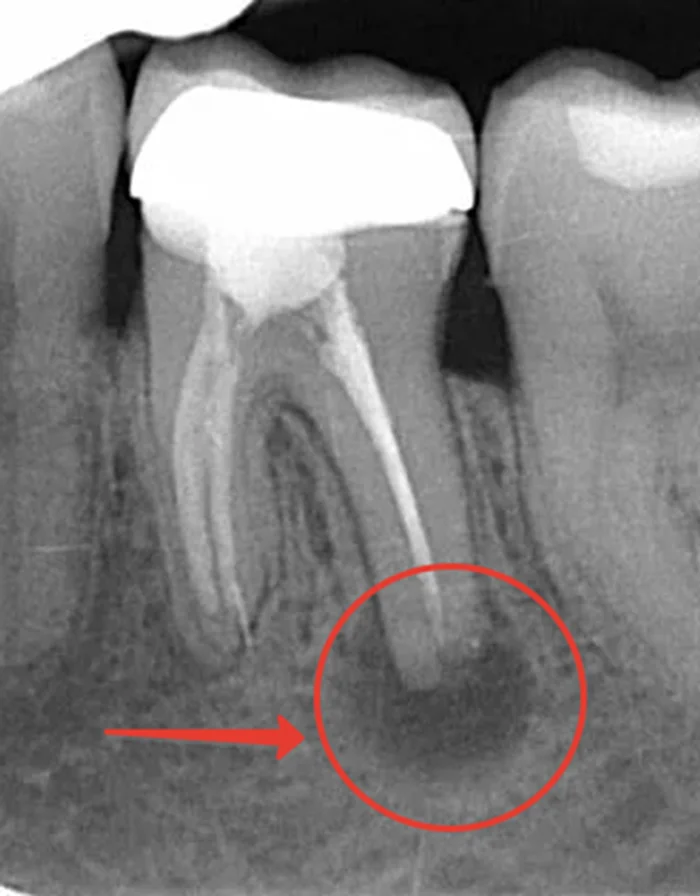

Это самый частый вопрос от пациентов, у которых на корне зуба обнаружили воспаление. И этот вопрос вполне логичный. Воспалительный очаг на верхушке корня, или в простонародье, киста, как правило, является осложнением кариеса и главной причиной потери зубов. Перед пациентом стоит выбор: удаление зуба с последующим протезированием или лечение такого зуба, но без каких-либо гарантий. По сути, выбираем между плохим или очень плохим вариантом. Коллегам сразу скажу, что я знаю, что киста- гистологический диагноз и правильнее говорить периодонтиты, очаги деструкции и т.д., но статья эта для широкой публики и моя задача, чтобы было всем максимально понятно. Договоримся, что все подобные штуки будем называть «киста». 2 ) Инфекция. Когда кариозная полость дошла до нерва и убила, то инфекция в поисках пропитания начинает переть за верхушку корня отчего поражается связка и костная ткань, окружающая зуб. Также причиной может служить недостаточно обработанный канал при удалении нерва. Вот пример из

2 ) Инфекция. Когда кариозная полость дошла до нерва и убила, то инфекция в поисках пропитания начинает переть за верхушку корня отчего поражается связка и костная ткань, окружающая зуб. Также причиной может служить недостаточно обработанный канал при удалении нерва.